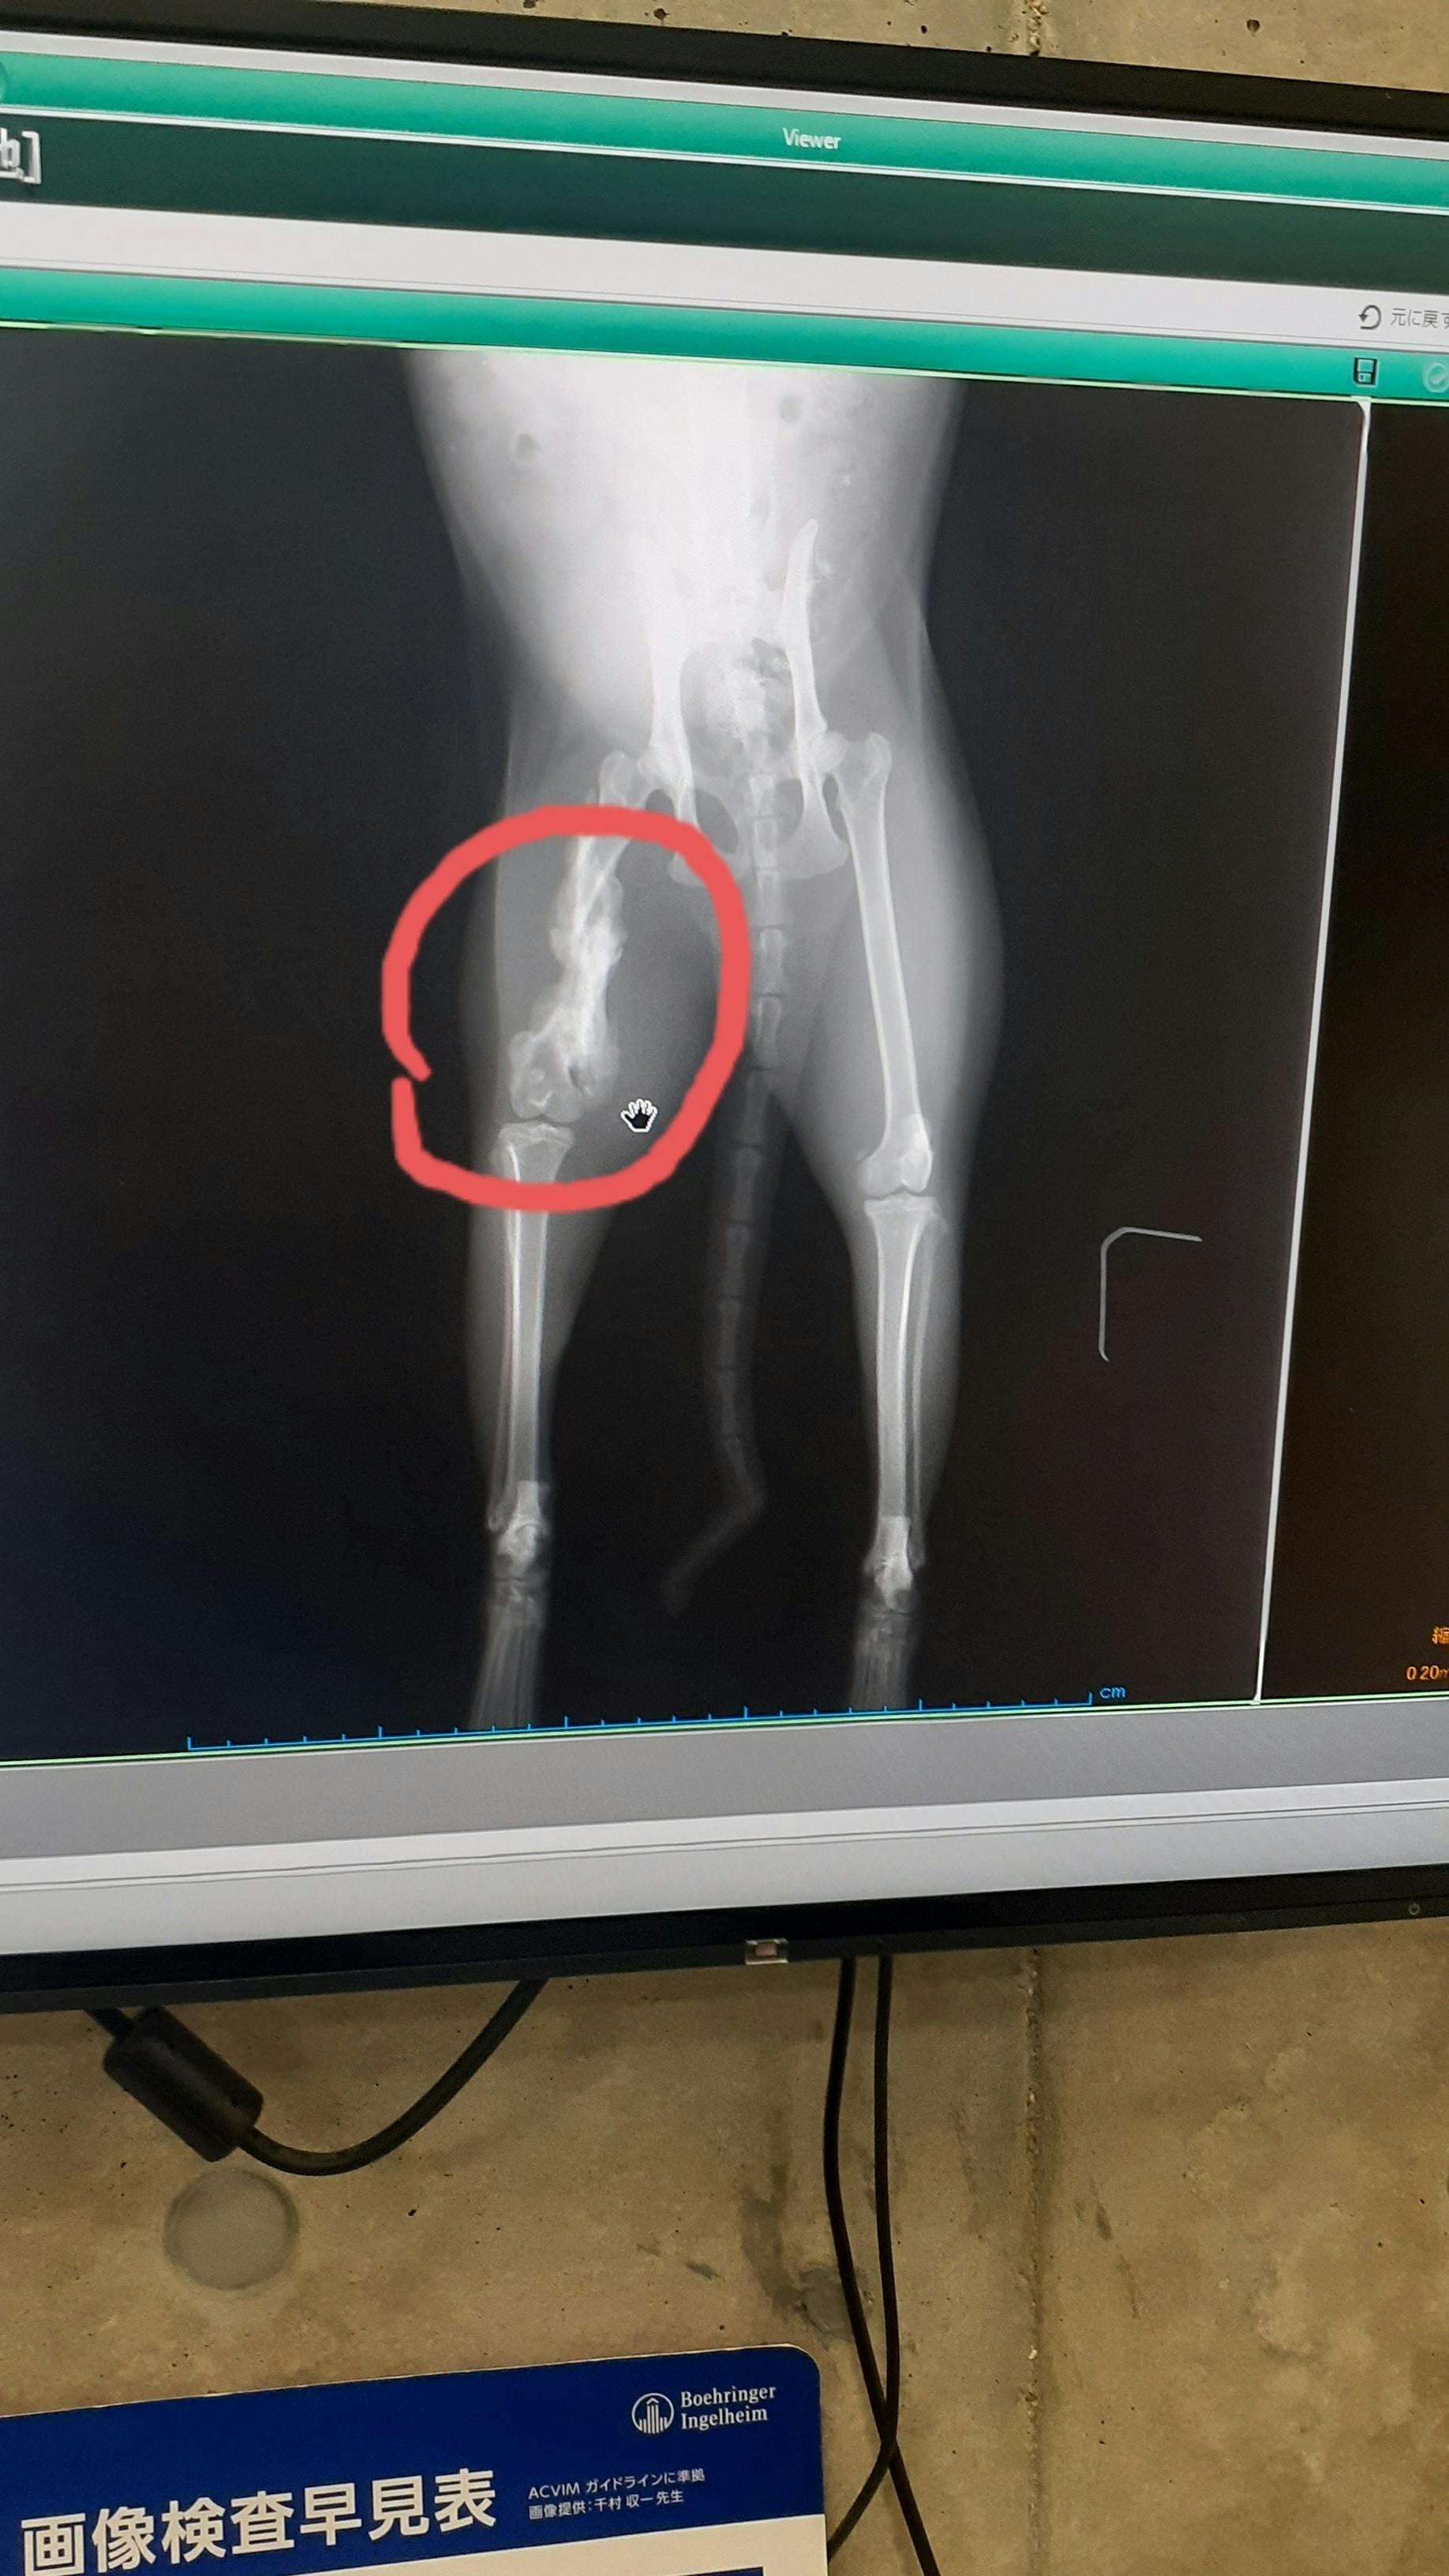

後ろ脚のレントゲンを取ってもらいました。

右脚上部に二ヶ所骨折の後が見付かり、そのずれた骨の周りにモジャモジャとしたまた骨らしきものが写りました。高齢だったら骨の腫瘍を疑うところだが

この子は歳が若いのでこれは自力で再生した後だと言うことでした。

足も左右で比べると明らかに右足が短くなりびっこを引くのは仕方なく、これはこの形でもう固まっているので治療する必要もなく、一生このままでびっこを引いて暮らすことになると言うことでした。ハンディ背負ってしまいましたが、お外でも、ほんとよく食べる子だったので骨折にも負けず、自力で治したのかな。痛かったやろうね。怪我の原因は何かの不慮の事故だろうということでした。最悪、腐ってきて断脚もあるかも?しれないと思っていたので最悪の事態は免れてほんと良かったです。